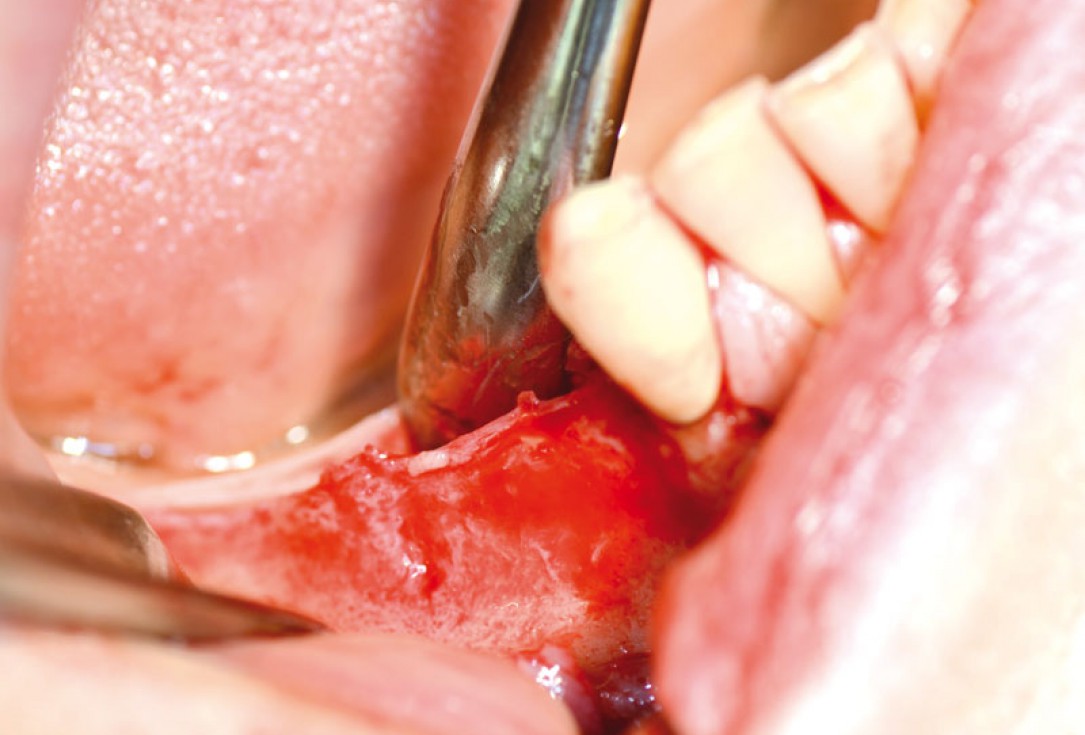

04/14 - Intraoperative situation: knife-edged ridge

Block augmentation with maxgraft® in the mandible - PD Dr. Dr. F. Kloss